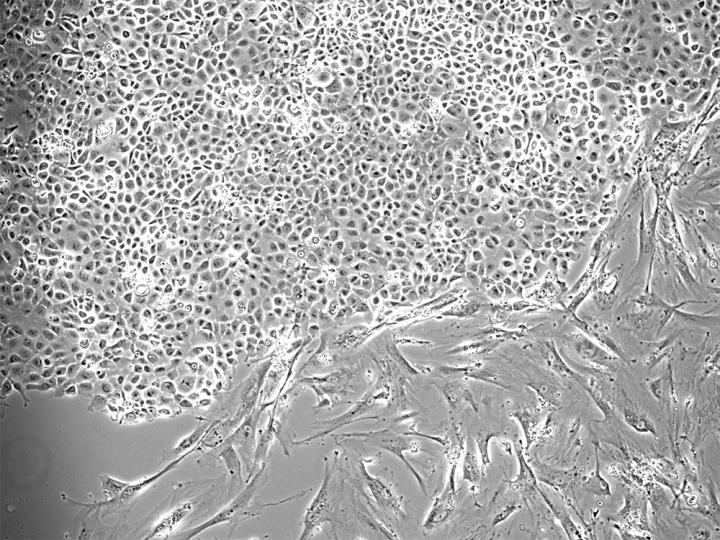

Stathopoulos and his team are working to understand the causes of pleural effusion, which remain unclear, in an effort to advance the treatment of this condition in the future. In the current study, the scientists examined cancer cells they had obtained from pleural effusions with a malignant mutation in the KRAS gene. KRAS is known to play a key role in the growth of various malignant tumors.

"We were able to show that these cells release a messenger substance into the bloodstream, which in turn attracts immune cells.* These cells then wander via the spleen to the pleural cavity, where they cause the effusion," Stathopoulos says, explaining the mechanism. In addition, the scientists found the KRAS-mutant cancer cells in the MPE material of lung cancer patients as well as in the cell lines derived from them.